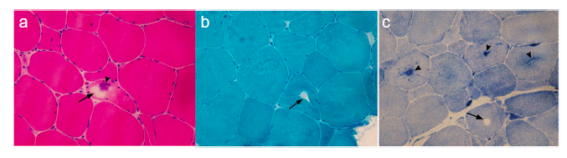

SCN4A基因突变相关的离子通道病肌肉活检病理变现可见肌纤维中出现管聚集及空洞。